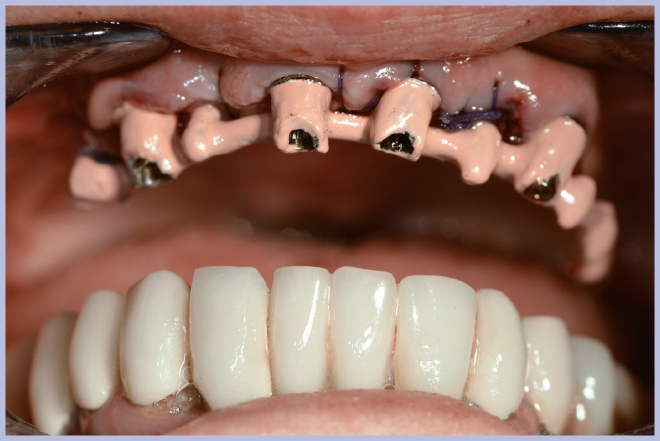

Sui monconi, dopo aver attivato la connessione a cono Morse (Fig. 3), sono state fissate le apposite cappette in titanio con le viti a testa alta (Fig. 4) ed è stata realizzata un’armatura di rinforzo per mezzo di una sincristallizzatrice intra-orale. In particolare la barra è stata ottenuta mediante saldatura sulle cappette di un filo pre-modellato di titanio grado 2 (Figg. 5, 6).

- Fig. 3 – Posizionamento dei monconi per protesi avvitata

- Fig. 4 – Fissaggio delle cappette in titanio

- Figg. 5, 6 – Struttura di rinforzo ottenuta saldando intra-oralmente un filo di titanio alle cappette